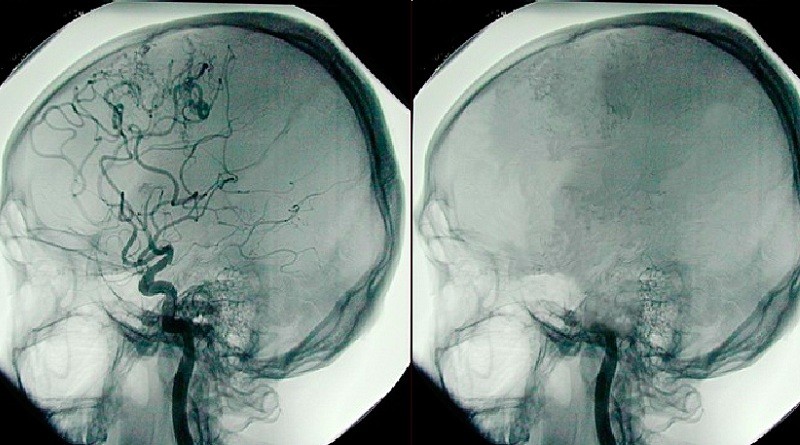

Beyin ölümü, tıbbi ölüm halini ifade eder. Beyin ölümünün geliştiği durumda kalp, böbrekler, akciğer ve karaciğer, solunum ve yaşam desteği sağlanması halinde kısıtlı bir süre daha çalışmaya devam eder. Peki ama beyin ölümü ne anlama gelir? Beyin hücrelerinin ölümü ne demektir? Beyin ölümü gerçekleştikten sonra ne olur? İşte detaylar...

Beyin ölümü tanısı konulduktan sonra hastanın tıbbi, geri dönüşümsüz ve yasal olarak öldüğü andan, kalbin durduğu ana kadar olan bir dönemdir. Beyincik ve beyin sapının kaybolduğu süreçte hastanın sadece kalbi atmaktadır. Dışarıdan bakıldığında sadece izlenebilen kalp atımlarıdır. Diğer yaşamsal fonksiyonlar yapay olarak tıbbi cihazlarla sağlanır. Kendi solunumu alamayan hasta cihazlarla solunum aldığı için, yaşam destekleri kesildiğinde hasta kaybedilir.

Beyin ölümünün tanısı için 4 uzmanın görüşü alınarak ortak bir karar verilmelidir. Hassas bir konu olan beyin ölümünün tam anlamıyla gerçekleşip, gerçekleşmediğini anlamak için bu 4 uzman kendi dallarına ait testler uygular. Uzmanlar; Anestezi uzmanı, Nöroloji uzmanı, Nöroşirürji uzmanı ve Kardiyoloji uzmanıdır.